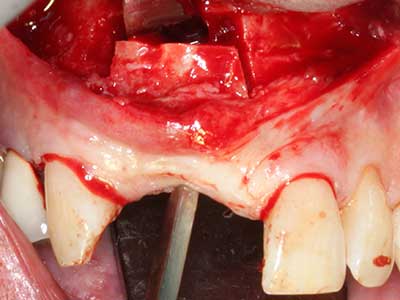

Il tessuto osseo non è semplicemente una struttura minerale, ma contiene anche una percentuale significativa di fibre di collagene. Ciò significa che non possiede solo una buona forza di compressione, ma anche un certo livello di flessibilità che è possibile sfruttare durante l'esecuzione degli accrescimenti di osso. Nella procedura di espansione classica con incisione ossea, la cresta alveolare atrofizzata viene incisa longitudinalmente ed espansa con cautela dopo aver raggiunto una profondità di osteotomia adeguata (figg. 13-16), idealmente senza una sostanziale rimozione del periostio (Brugnami, Caiazzo et al. 2014, Stricker, Fleiner et al. 2014). I sistemi a piastra e vite con distanza di espansione incrementale si sono dimostrati efficaci nella separazione delle due lamelle ossee restando al di sotto della soglia di frattura. In generale, sono richieste larghezze dell'osso residuo di almeno 3-4 mm (Chiapasco, Zaniboni et al. 2006) per garantire un'adeguata flessibilità e una copertura sufficiente dell'osso per gli impianti futuri. Se necessario, un'osteotomia di rilascio verticale su uno o più lati può migliorare la flessibilità. Una combinazione con ulteriori tecniche di accrescimento, in particolare dal lato buccale, è stata descritta come un'alternativa alla tecnica classica.

La procedura di incisione è particolarmente atraumatica e non comporta una perdita significativa di dimensione durante l'utilizzo delle seghe piezoelettriche, così come non si notano differenze rilevanti tra impianti in mandibole incise e impianti in una cresta alveolare senza deficit osseo (Chiapasco, Zaniboni et al. 2006, Danza, Guidi et al. 2009). Una sufficiente irrigazione continua è essenziale, tuttavia, in particolare con incisione profonda e localmente ristretta, per prevenire la sollecitazione termica nelle regioni apicali dell'osteotomia.